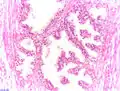

- Гістологічна структура простати

Нормальна гістологічна структура простати

Гістологічна структура простати при ДГПЗ